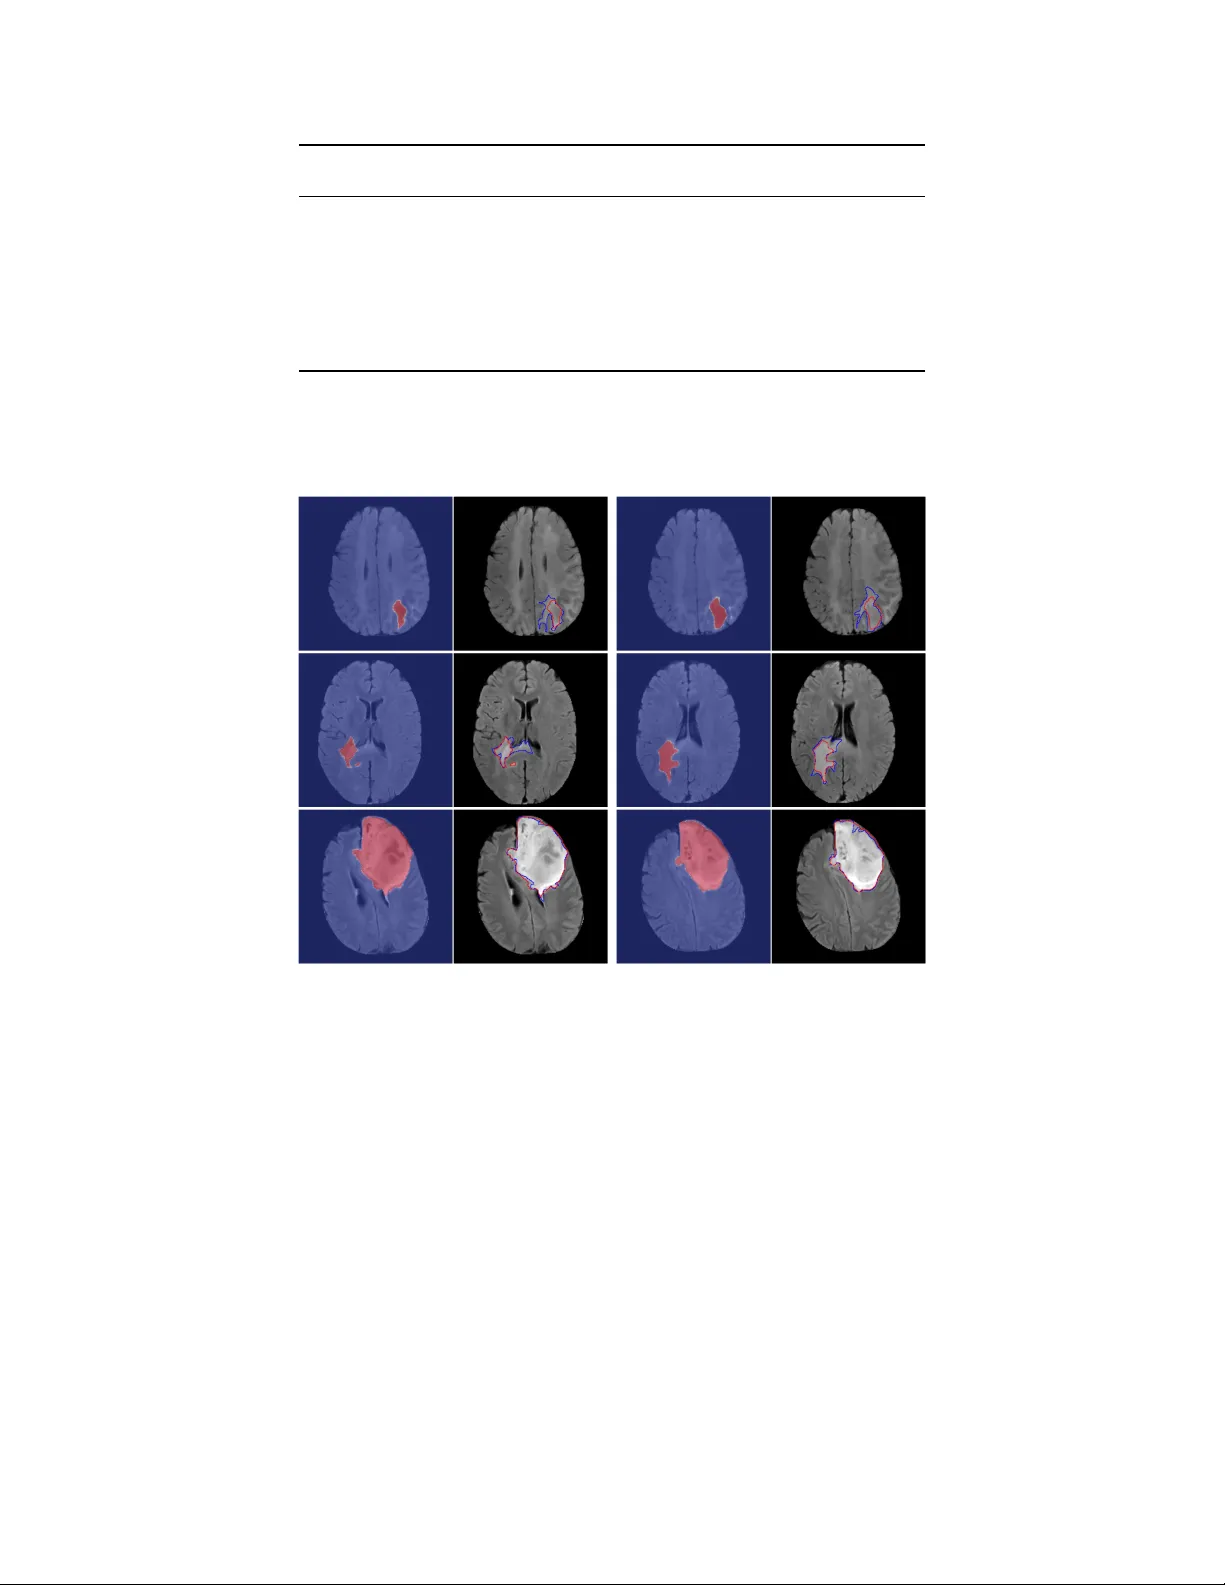

본 연구는 딥러닝 기반 U‑Net 모델을 이용해 저등급 교모세포종(LGG)의 MRI 영상을 자동으로 분할하고, 3가지 형태학적 지표(각도 표준편차, 경계 타원 부피비, 마진 변동)를 추출한다. 110명의 환자(5개 기관)에서 추출된 지표와 6가지 유전체 클러스터(IDH/1p19q, RNASeq, DNA 메틸화, 복제수, miRNA, 클러스터‑오브‑클러스터)를 Fisher 정확 검정으로 연관성을 탐색했으며, Bonferroni 보정 후 p<0.0…

본 논문은 저등급 교모세포종(LGG)의 방사선유전체학 연구에 딥러닝 기반 자동 종양 분할과 형태학적 특징 추출을 적용하여, 이들 특징이 기존에 정의된 유전체 아형과 통계적으로 연관되는지를 검증한다. 연구는 총 110명의 환자를 대상으로 진행되었으며, 이들은 TCGA와 TCIA에서 확보한 MRI(FLAIR 중심)와 6가지 유전체 클러스터(IDH/1p19q, RNASeq, DNA 메틸화, 복제수, miRNA, 클러스터‑오브‑클러스터) 데이터를 보유하고 있다. 환자들은 5개 기관에서 모집되었고, 데이터는 22개의 교차검증 폴드(각 5명)로 나누어 모델 학습·평가에 활용되었다.

전처리 단계에서는 이미지 스케일링, 스컬 스트리핑, 히스토그램 기반 윈도우 조정, Z‑score 정규화를 수행해 서로 다른 스캔 간 강도 차이를 최소화하였다. 분할 모델은 2D U‑Net 구조를 채택했으며, 입력 채널은 전·후 조영제와 FLAIR을 포함한 3채널 혹은 FLAIR만 사용할 경우 인접 슬라이스를 보조 채널로 사용했다. 종양이 차지하는 픽셀 비율이 매우 낮아 오버샘플링 전략을 적용했으며, 각 종양 슬라이스를 3번 복제하고 회전·스케일 변형을 가해 데이터 다양성을 확보했다. 학습 후에는 3D 연결성 분석을 통해 가장 큰 연결 컴포넌트만을 남겨 false positive를 제거하는 후처리를 수행했다. 교차검증 결과 평균 Dice 계수는 0.82(±0.04)로 인간 전문가 수준에 근접했다.

분할된 종양에 대해 세 가지 2D·3D 형태학적 지표를 계산했다.

1. **각도 표준편차(ASD)**: 종양 중심에서 10개의 등각 구간으로 방사 거리를 측정하고, 각 구간의 표준편차를 평균한 값. 방사 거리들을 평균 1로 정규화해 크기 의존성을 배제한다.

2. **경계 타원 부피비(BEVR)**: 종양 부피와 최소 경계 타원의 부피 비율. 값이 클수록 종양이 구형에 가깝고, 작을수록 불규칙성을 나타낸다.

3. **마진 변동(MF)**: 종양 경계 거리 시계열에 10% 길이의 평균 필터를 적용한 전후 차이의 표준편차. 고주파 변동성을 반영해 경계의 거칠기를 정량화한다.